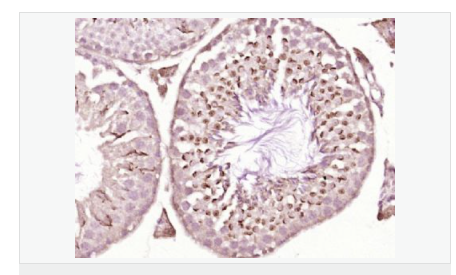

| 產品應用 | WB=1:500-2000 ELISA=1:5000-10000 IHC-P=1:100-500 IHC-F=1:100-500 Flow-Cyt=1ug/test ICC=1:100-500 IF=1:50-200 (石蠟切片需做抗原修復) not yet tested in other applications. optimal dilutions/concentrations should be determined by the end user. |

| 細胞定位 | 細胞核 細胞漿 |